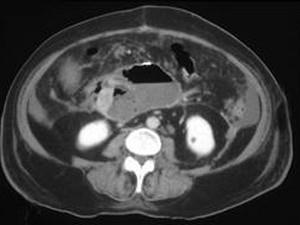

问题 女,33岁,发热,中上腹压痛反跳痛,血清淀粉酶增高,CT检查如图,最可能的诊断是 ( )

选项 A、胰腺假性囊肿 B、胰腺癌 C、慢性胰腺炎 D、胰腺脓肿 E、急性胰腺炎

答案 D